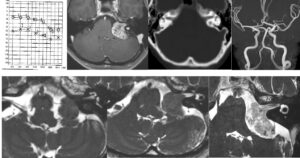

手術は通常通り行われ、顔面神経の麻痺を起こさずに摘出は終了し、うまくいったと考えていました。しかし術後より覚醒障害が続き、強い小脳腫脹を生じたため、術後脳室ドレナージ術、バルビタール麻酔療法、気管切開まで行い急性期を乗り切りました。術前より下肢静脈血栓症を合併していたことと、Petrosal veinが通常より広範囲の静脈環流を行っていたためと考えられます。現在、覚醒し、四肢が動くようになってきました。

手術は通常通り行われ、顔面神経の麻痺を起こさずに摘出は終了し、うまくいったと考えていました。しかし術後より覚醒障害が続き、強い小脳腫脹を生じたため、術後脳室ドレナージ術、バルビタール麻酔療法、気管切開まで行い急性期を乗り切りました。術前より下肢静脈血栓症を合併していたことと、Petrosal veinが通常より広範囲の静脈環流を行っていたためと考えられます。現在、覚醒し、四肢が動くようになってきました。